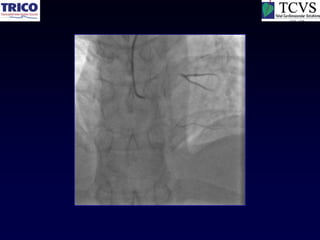

RCA CTO